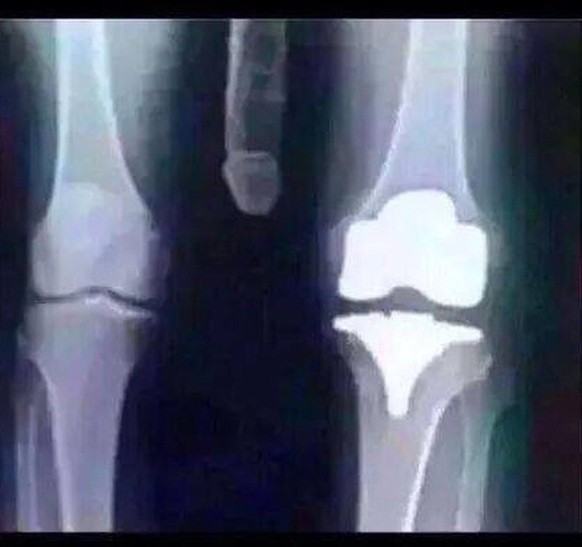

Vous voyez ce qui est atypique ici?

Tada!